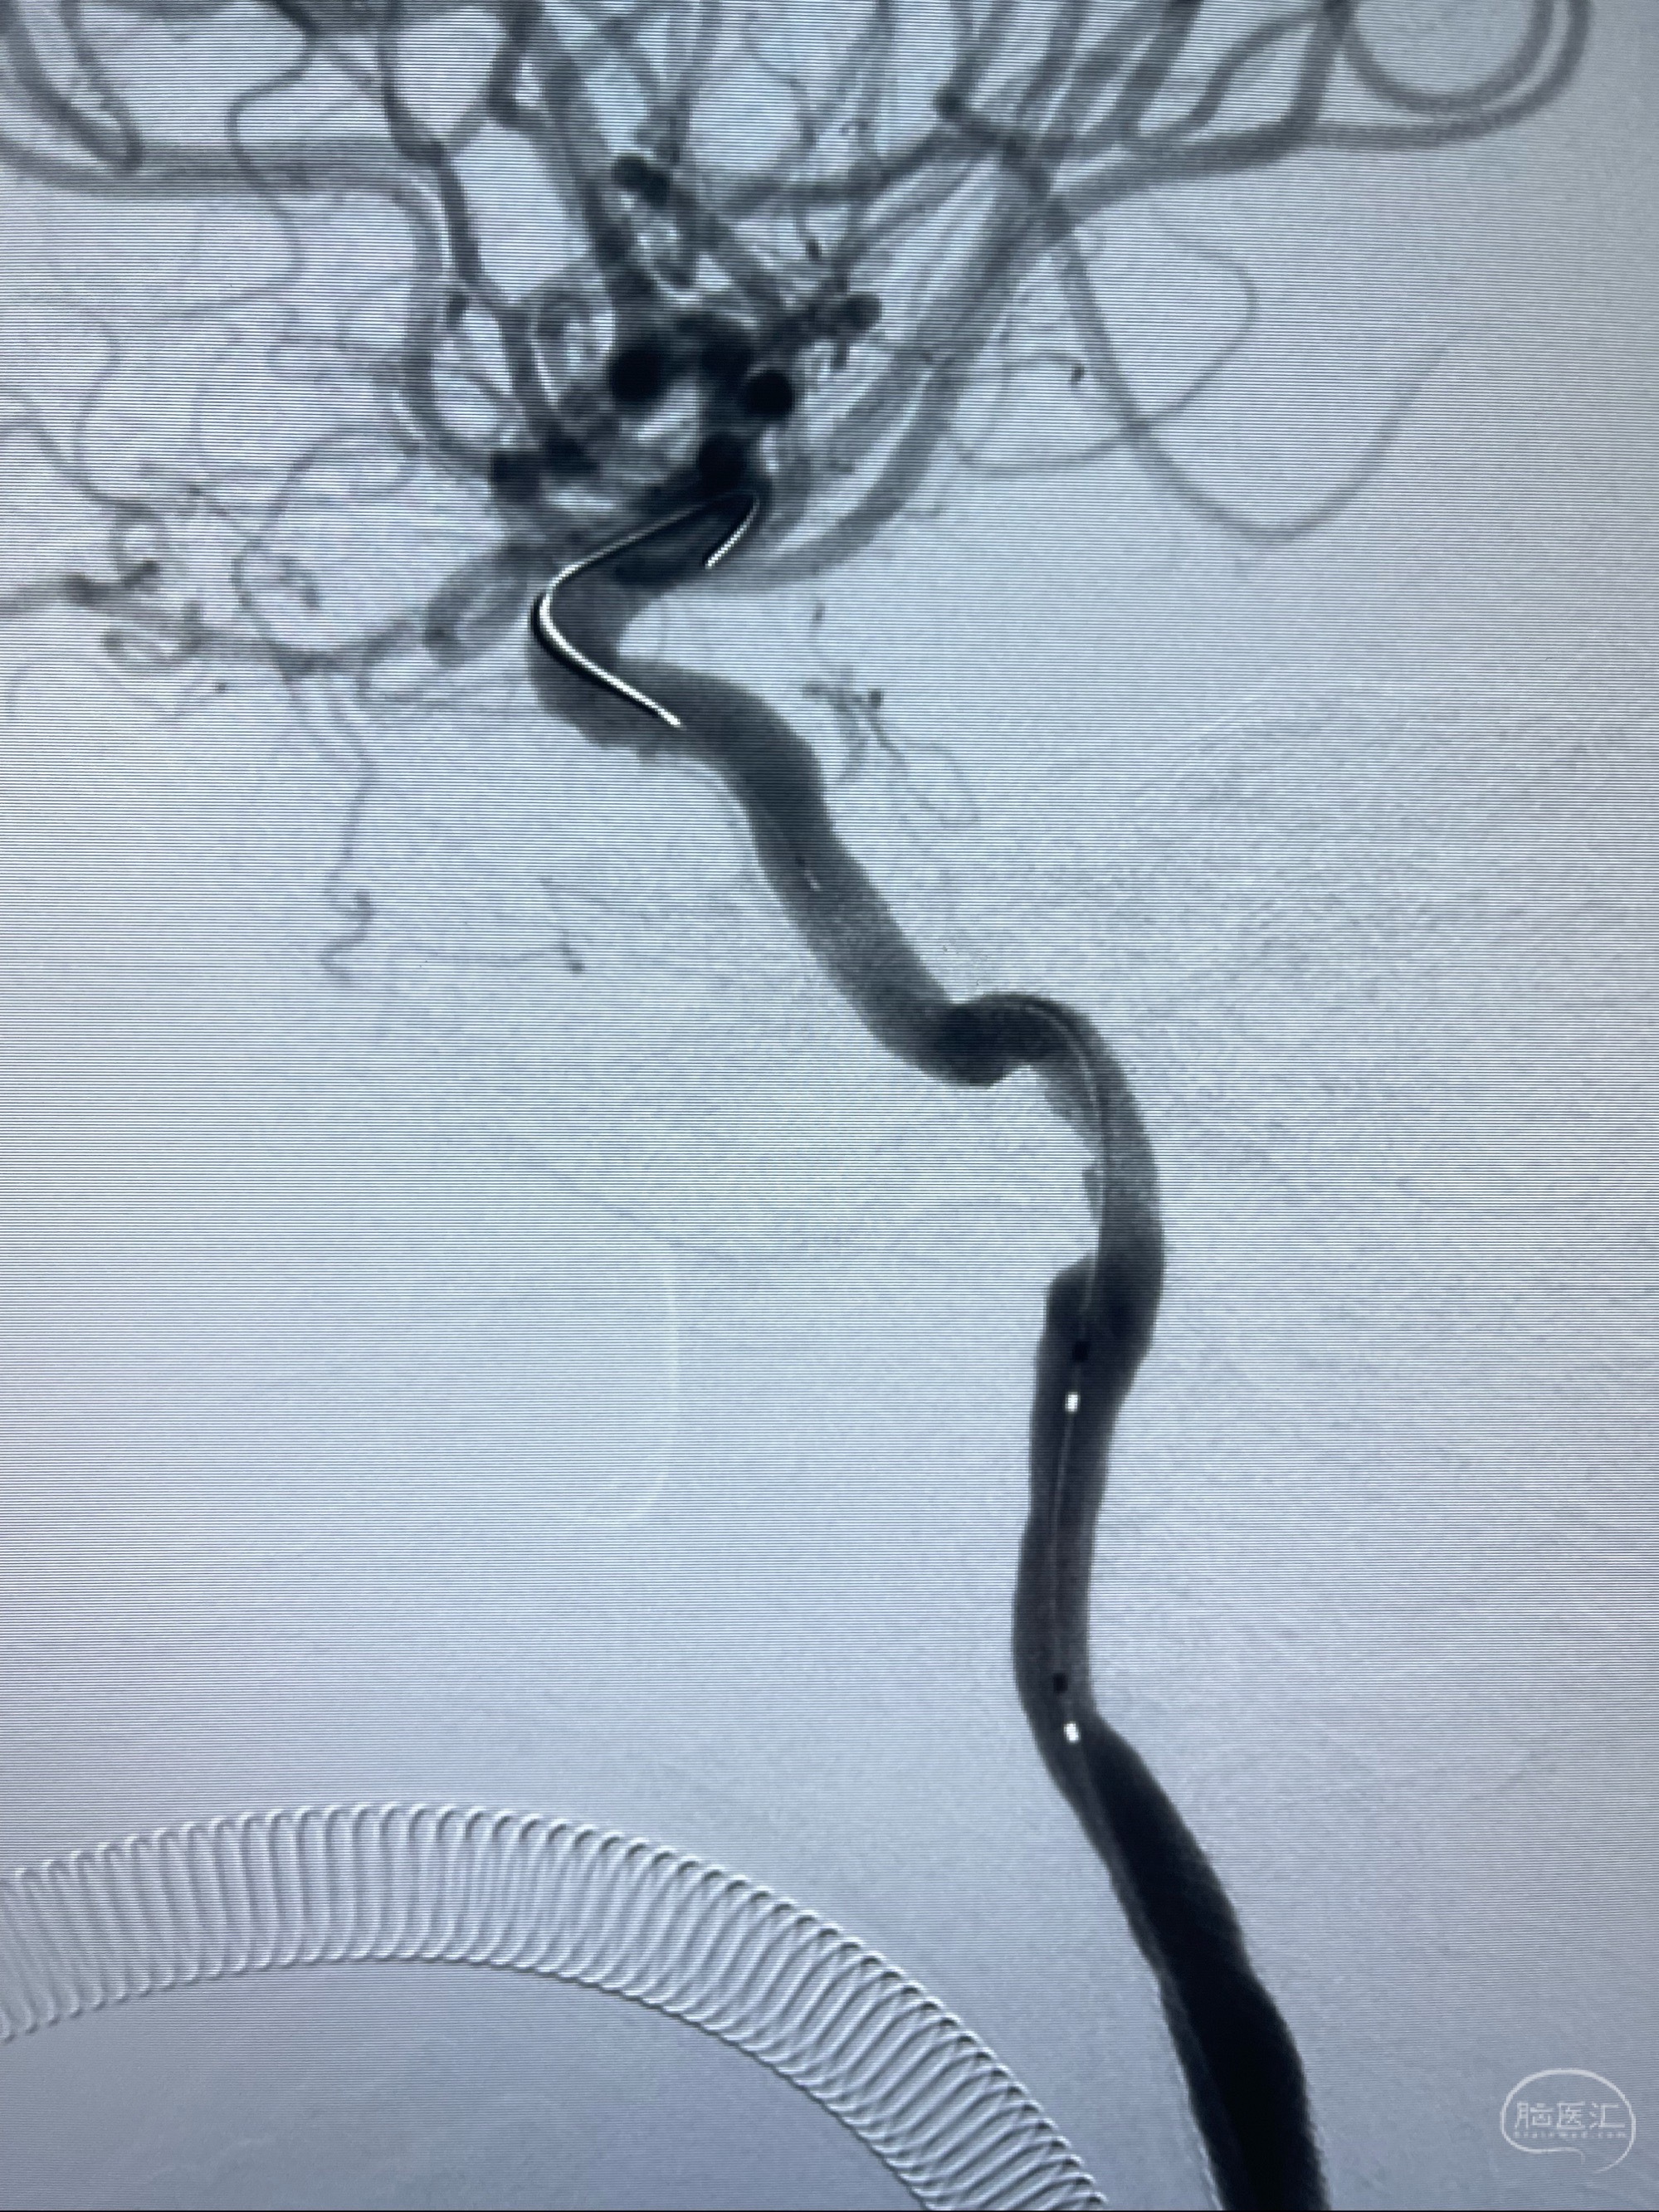

2023-07-10DSA:右侧颈内动脉岩骨段夹层伴中偏重度狭窄改变,左侧颈总动脉闭塞、右侧颈外动脉由右侧肋颈干甲颈干吻合代偿

箭头所示为颈内动脉岩骨段重度狭窄,结合MRI,考虑为肿瘤侵犯右侧颈内动脉

箭头以近至支架段管腔不规则狭窄

088NeuroMAX100cm长鞘在125cmMPA及黑泥鳅导丝引导下超选择性插入右侧颈内动脉支架内

经导引导管造影显示支架远端颈内动脉不规则狭窄伴局部充盈缺损,同时行全身肝素化5ml